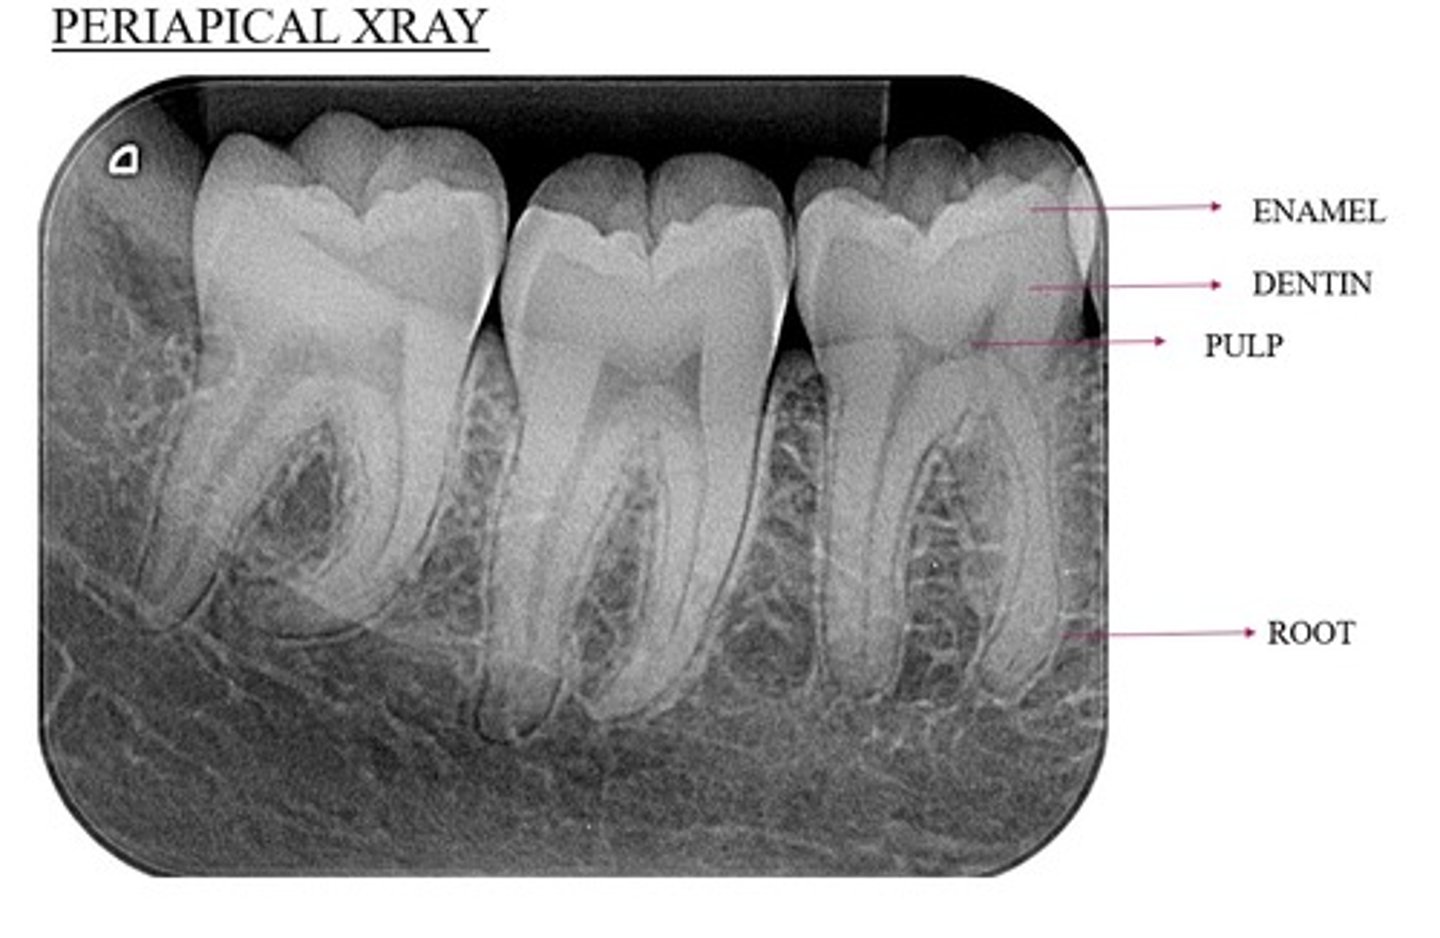

Example of a periapical x-ray:

What anatomy is demonstrated in periapical imaging? What kind of information?

• Provides detailed information about the teeth and the surrounding alveolar bone

• Demonstrates crown to apex.

• At least 2mm bone, ideally 5mm beyond apex.